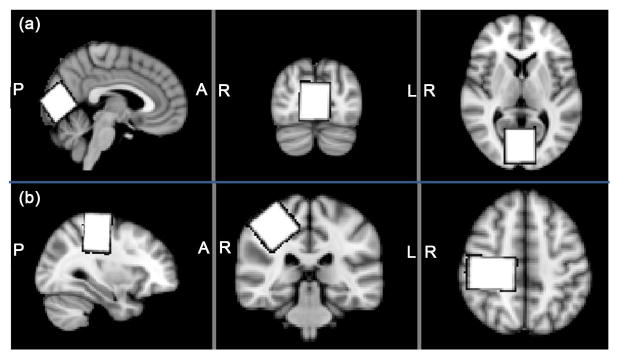

The purpose of the present study was to assess the reproducibility of voxel placement for GABA-edited MRS. GABA-edited MRS data were acquired in 13 healthy volunteers from (3 cm)3 voxel; and within the same session a second acquisition was independently prescribed. A three-dimensional voxel mask image was reconstructed in T1-image-space using the SVMask tool (in house software). Reproducibility of voxel placement was assessed using the Dice overlap coefficient, both within-subject and between-subject following co-registration of T1 images and transformation of voxel mask images to standard space. Within-subject overlap coefficients were 86% ± 5%. Between-subject overlap coefficients were 75% ± 10%. For the two voxel locations considered (occipital and sensorimotor), voxel overlap was very similar. Between-subject values are higher due to between-session effects, anatomical variability and volume mismatch in standard space. While surprisingly low in terms of volume overlap, the overlap coefficients correspond to acceptable linear displacements.